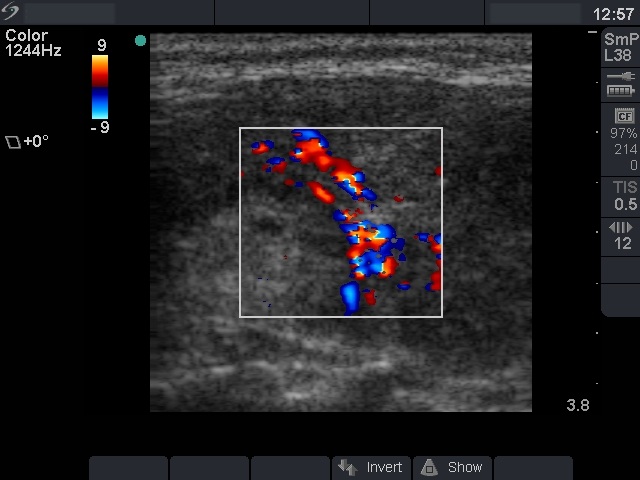

Ultrasonography: the thyroid was hypoechogenic with two well-circumscribed hyperechogenic areas in the right lobe. These were surrounded with a halo and presented perinodular blood flow.